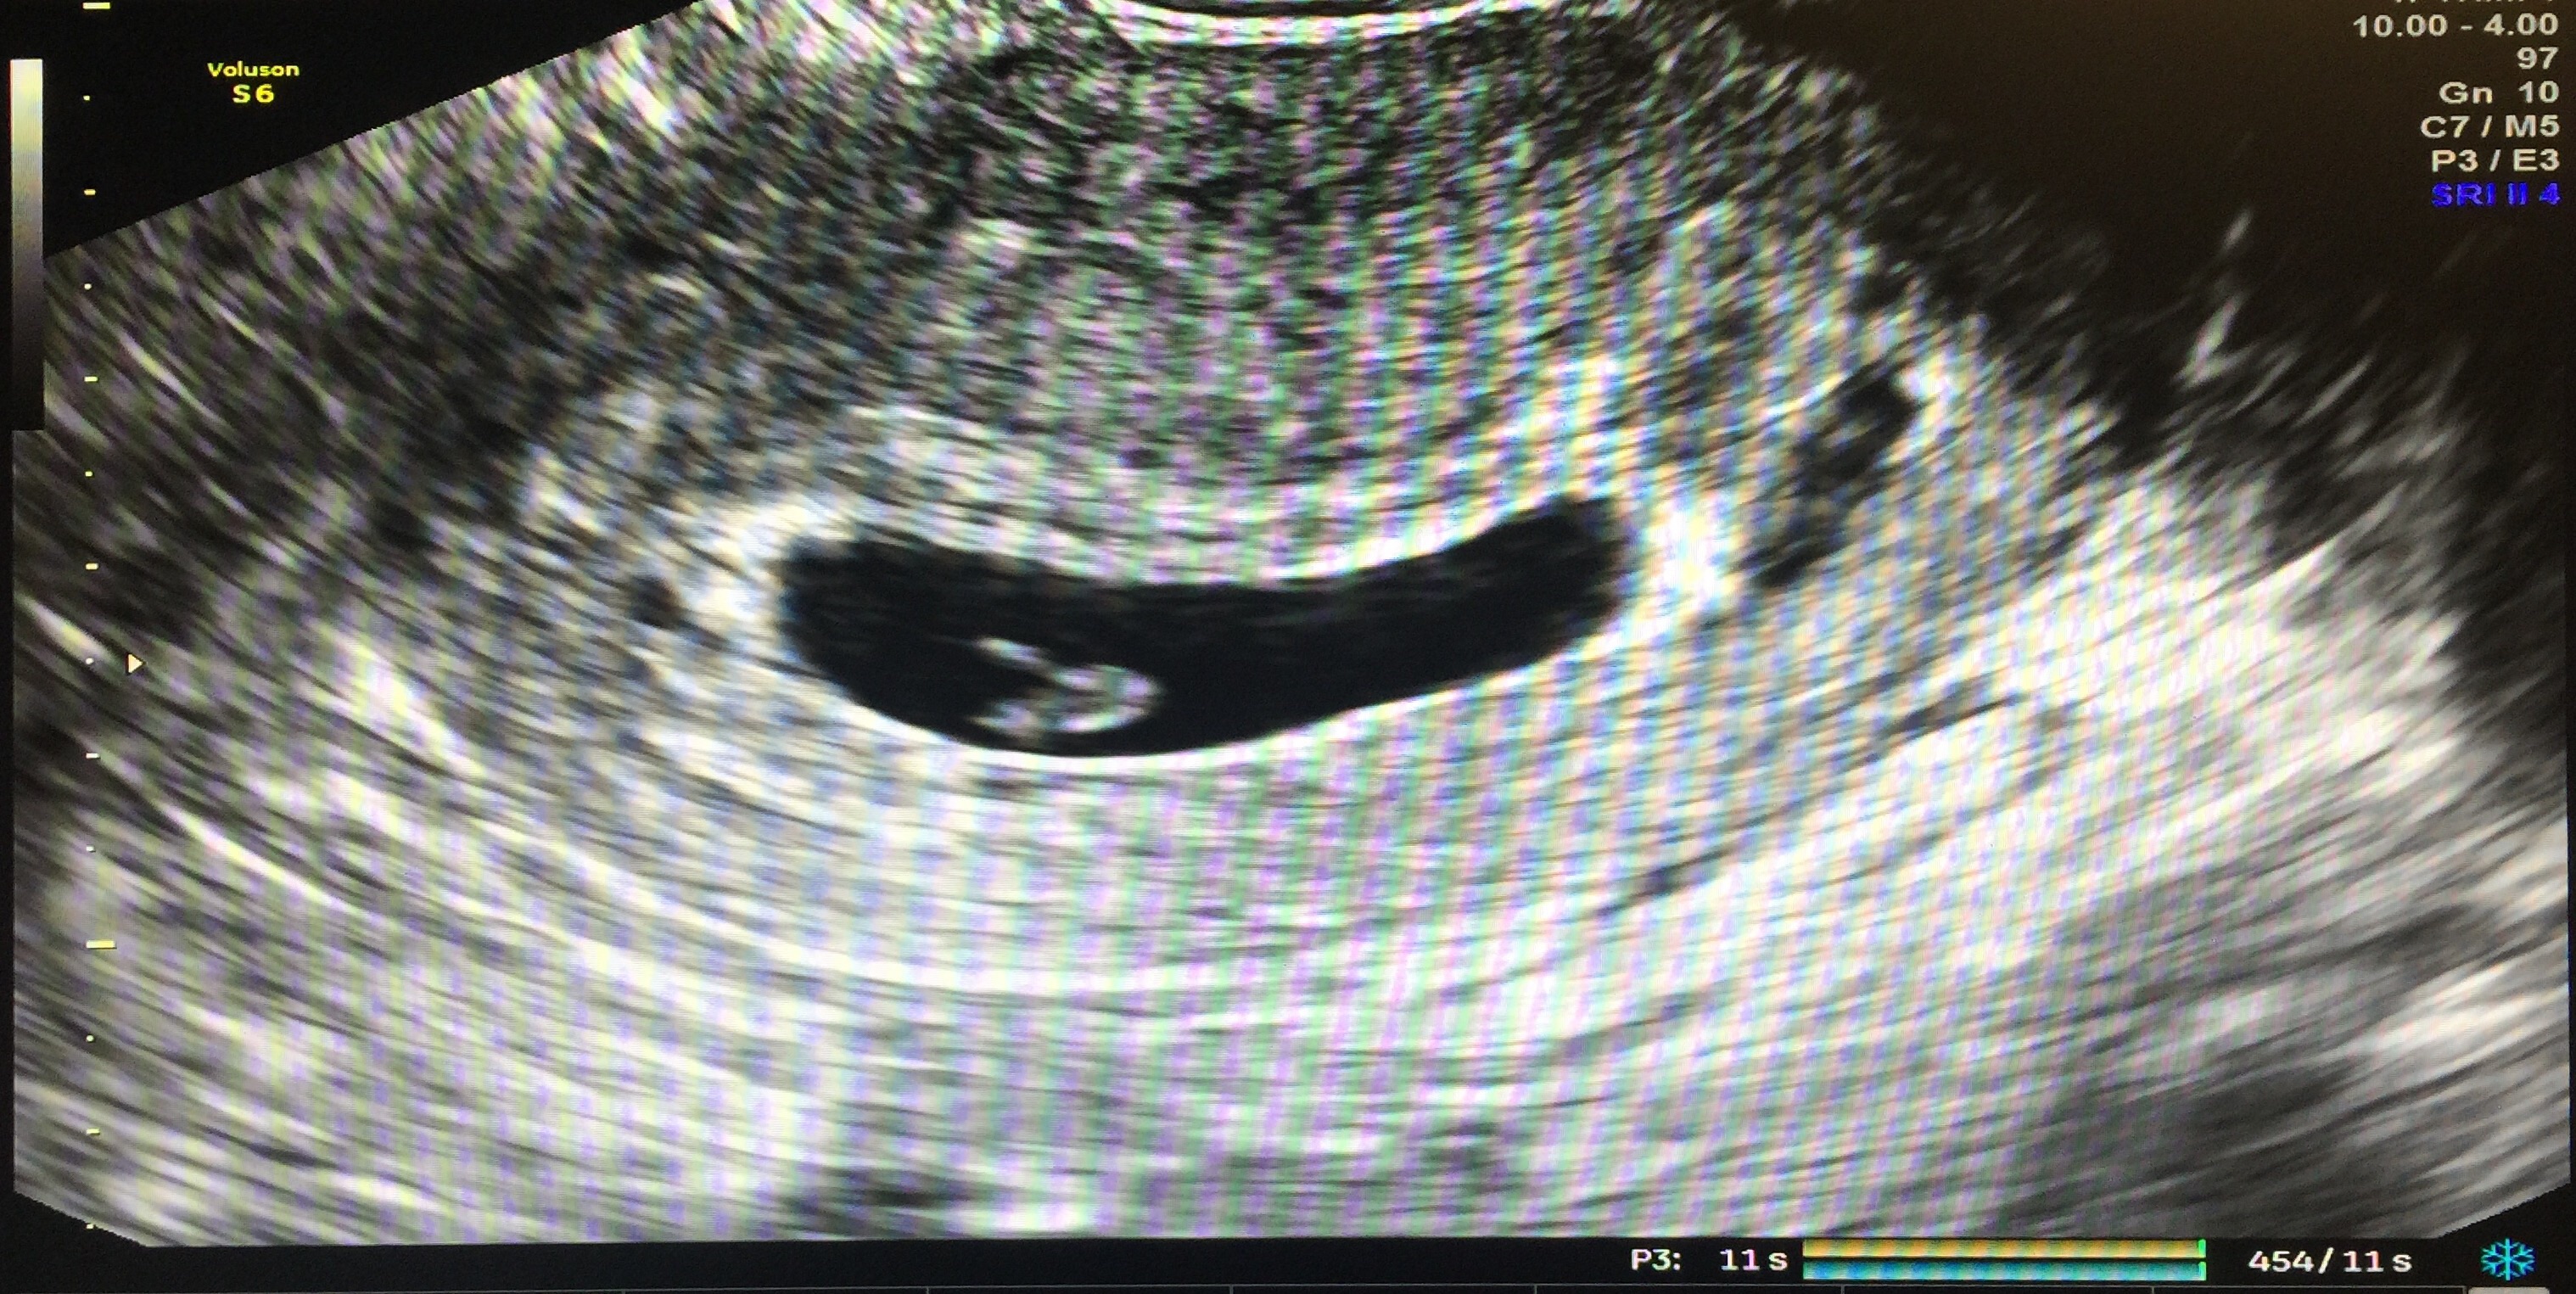

This was a transabdominal ultrasound.